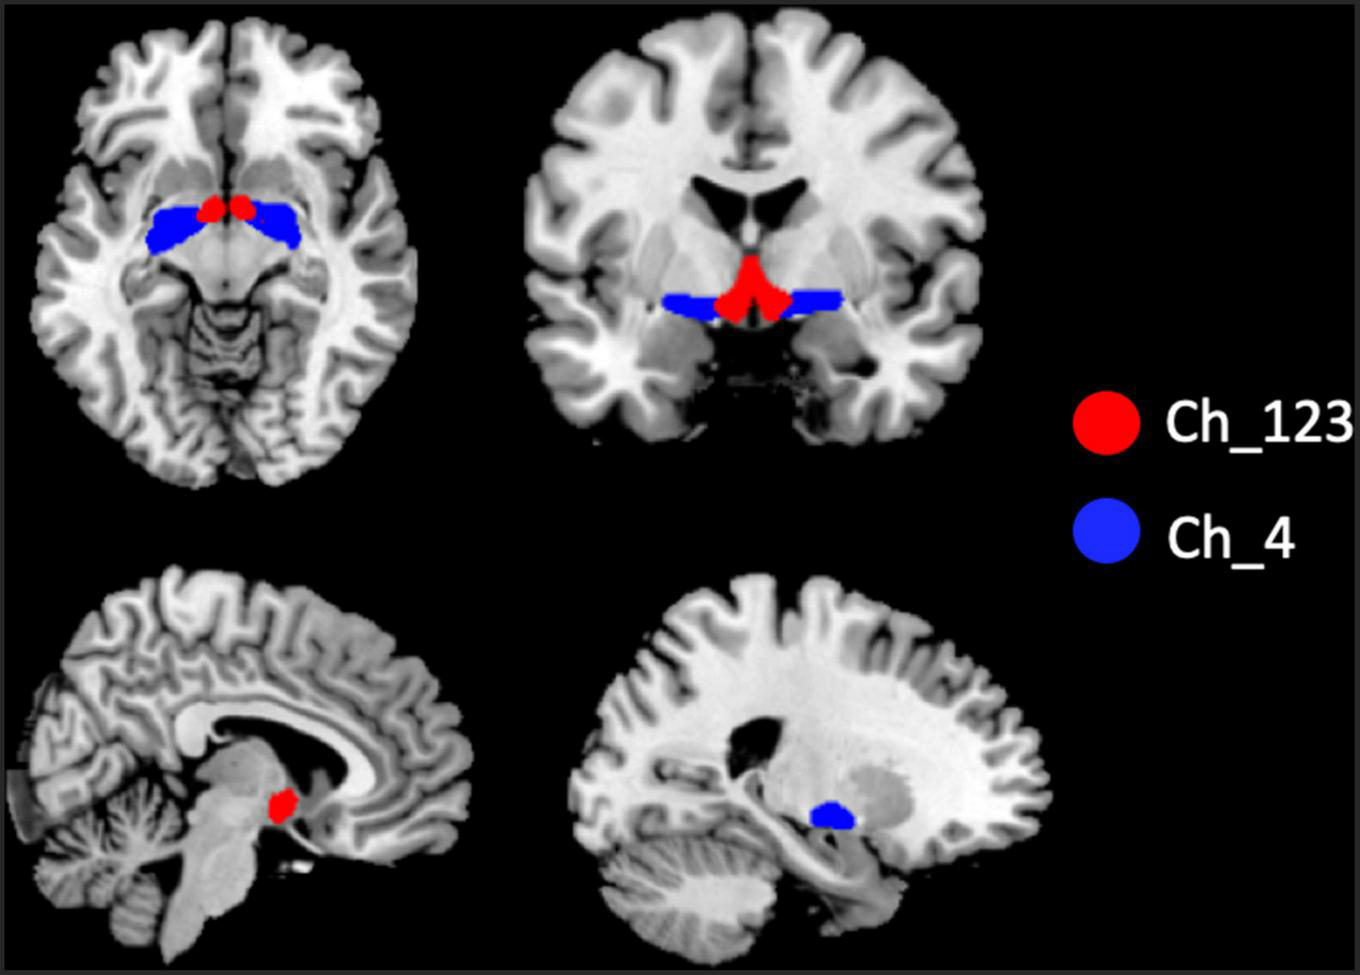

The two BF subregions, Ch_4 and Ch_123 covering both left and right hemispheres (Figure 1), were generated from the BF probabilistic maps in the SPM Anatomy toolbox (25, 34). The reasons we chose to use the BF probabilistic maps are as follows. First, the probabilistic cytoarchitectonic map of BF has been widely used in previous studies (35–38); Second, a recent study revealed that BF is functionally organized into two subdivisions that largely follow anatomically defined boundaries of Ch_123 and Ch_4 (28). The two seed regions were resampled to MNI space, in correspondence with the normalized rs-fMRI data. FC analysis of the two seed regions was conducted in a voxel-wise manner. For each seed region, voxel-wise FC maps were calculated by correlating voxel-wise the mean time series across a certain BF subnucleus with all time series across the brain. To assure the normality of FC correlation coefficient maps, the correlation coefficients were converted to z-values using Fisher’s transformation. Finally, the obtained z-maps were smoothed with a 6-mm full width at half maximum (FWHM) isotropic Gaussian kernel. The flow chart of the seed-based FC analysis was shown in Figure 2.

FIGURE 1

Illustration of the locations of basal forebrain (BF) subregions. The red color represents Ch_123; the blue color represents Ch_4.